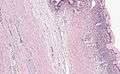

Pancreatic mucinous cystadenoma

Pancreatic mucinous cystadenoma, also known as "mucinous cystadenoma of the pancreas", is a benign tumour of pancreas. It is one of the cystic lesions of the pancreas.[1]

Microscopy

Mucinous cystadenoma of the pancreas